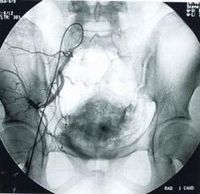

外陰白斑病外陰的病損範圍不一,主要累及大 陰唇、陰唇間溝、 陰蒂包皮、陰唇後聯合等處,長呈對稱性。早期病變較輕時,皮膚顏色呈暗紅色或粉紅色,角化過度部位則呈 白色。由於長期的搔抓和摩擦,皮膚增厚似皮革,色素增加,皮膚紋理明顯突出,皮嵴隆起,呈多數小多角性扁平 丘疹,並群集成片,出現苔癬樣變,故臨床上亦稱此病為慢性單純性苔癬。由於局部潮濕、搔抓和摩擦的 程度不同,以及對局部用藥的反應不一,患者不同部位的病損 形態有差別,嚴重者可因搔抓引起 表皮抓破、皸裂、潰瘍。